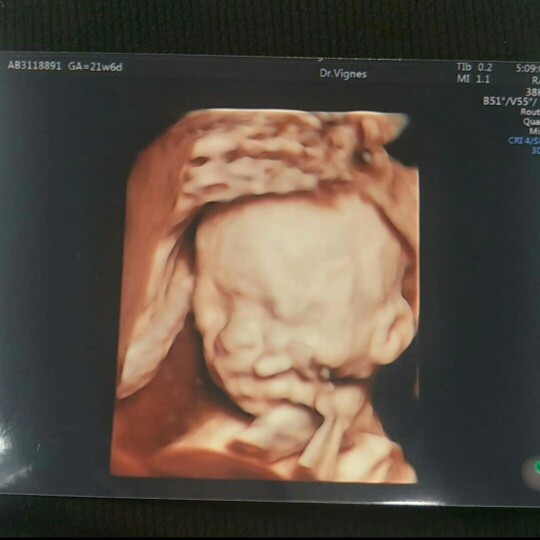

แก้มป่องๆ❤️รูปตอน27วีคจ้า ตอนนี้ 33วีคแล้วจ้า